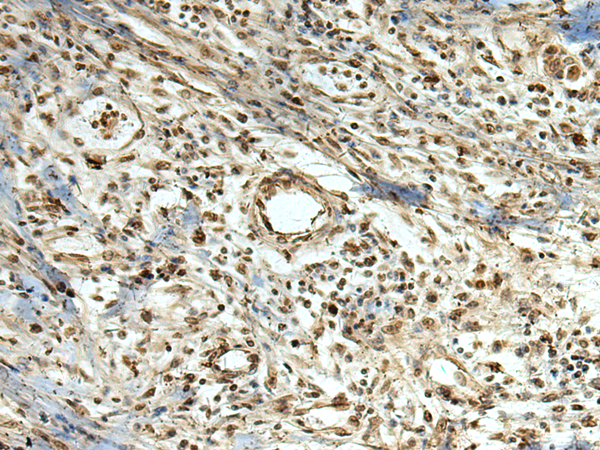

分类: 科研抗体货号: P03349别名: C1orf71; PPP1R64应用: WB,IHC反应种属: Human, Mouse